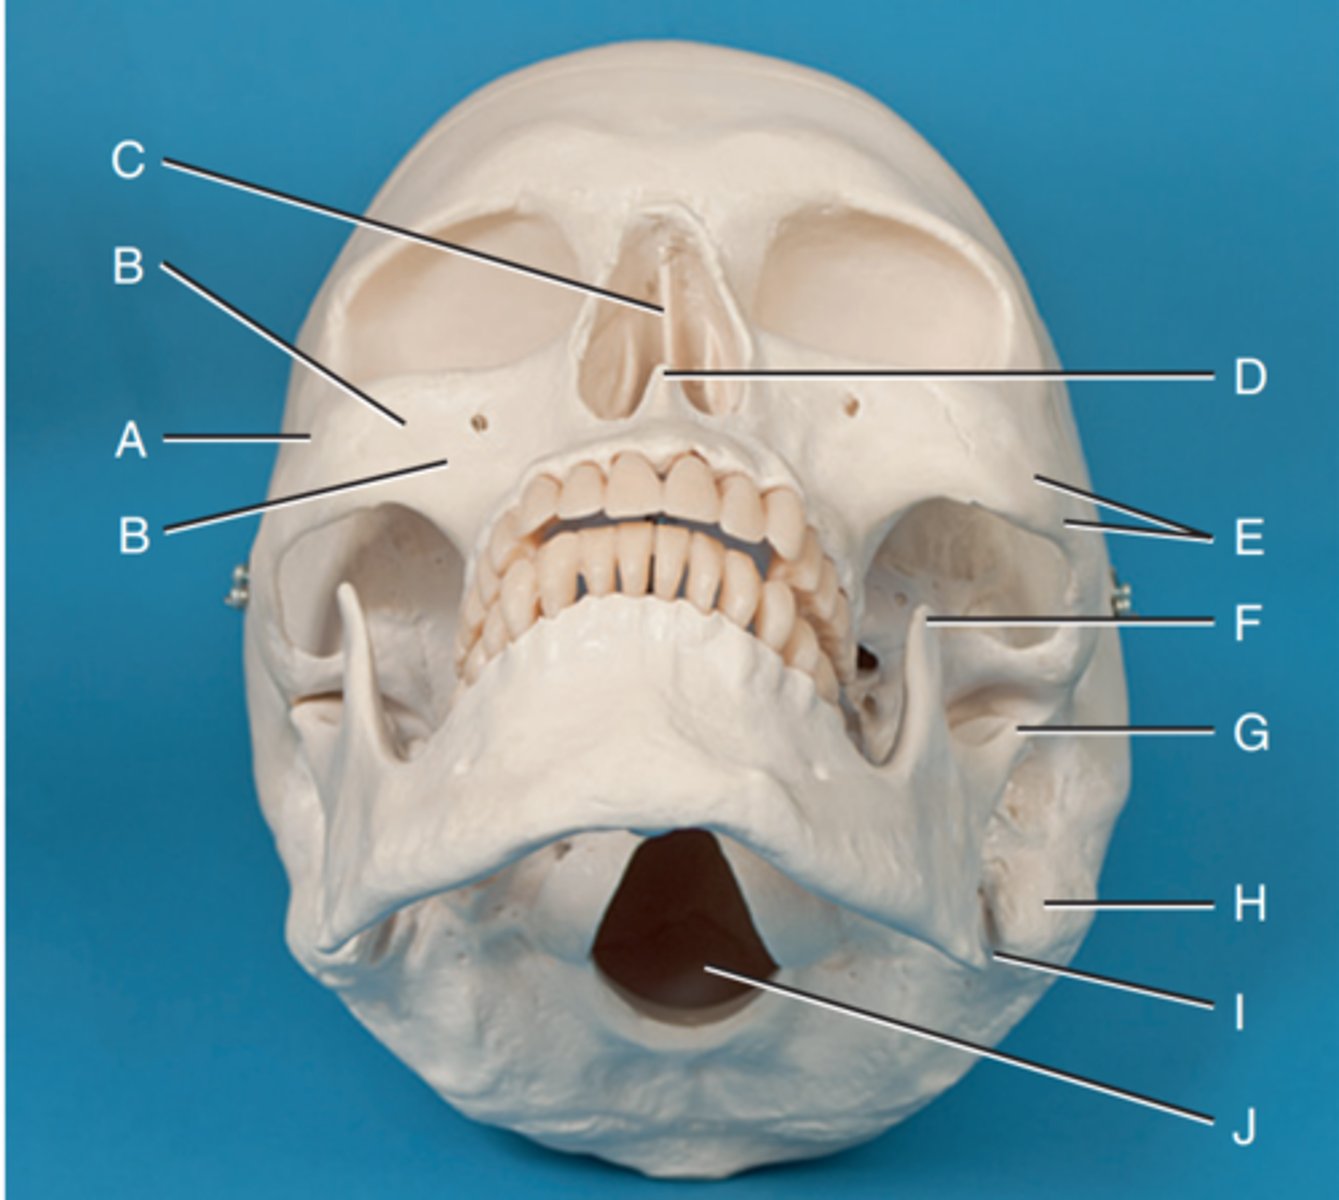

Zygomatic prominence

Label A

Body of maxilla

Label B

Bony nasal septum

Label C

Anterior nasal spine

Label D

Zygomatic arch

Label E

Coronoid process

Label F

Condyle

Label G

Mastoid process of temporal bone

Label H

Angle of mandible

Label I

Foramen magnum

Label J